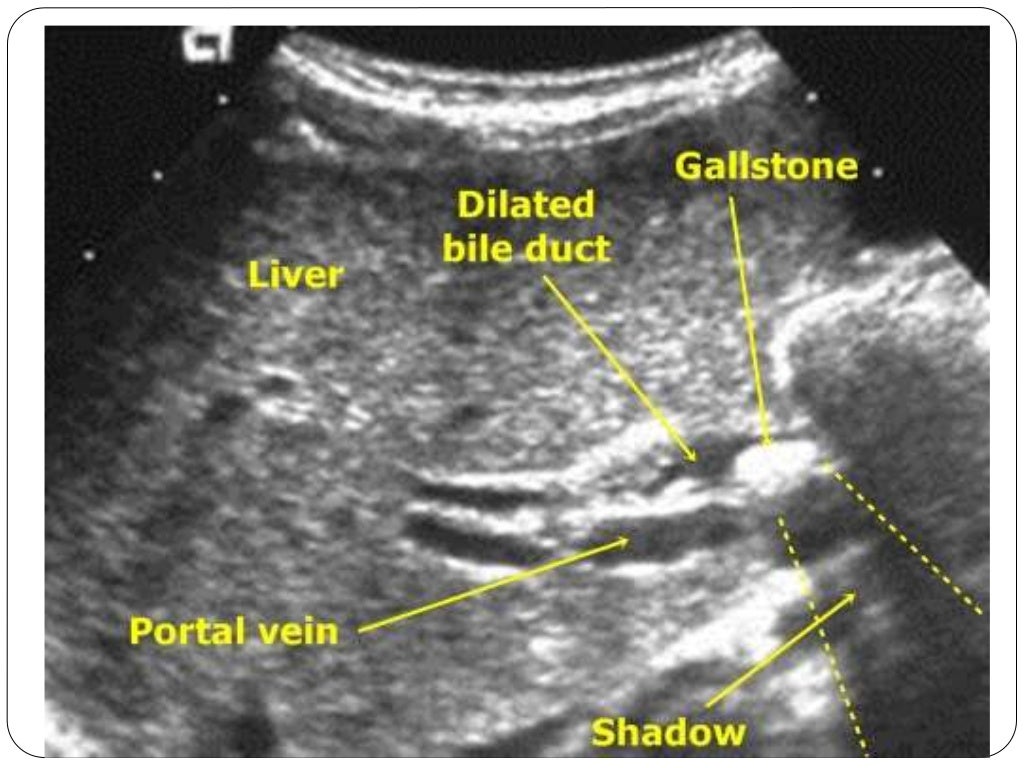

Jaundice Dog Differentials . Radiology and ultrasonography are the imaging modalities most often used to evaluate icteric patients. differentials for hyperbilirubinemia can be categorized as prehepatic, hepatic, and posthepatic icterus. Jaundice is clinically detectable when the plasma concentration of bilirubin exceeds 30. if the animal is moderately or markedly anaemic (approx pcv < 25% in dogs, pcv < 20% cats), then the icterus is very likely to. the term icterus is used interchangeably with jaundice to refer to yellow discoloration of skin, mucous membranes, and sclerae caused by an accumulation of bilirubin pigment in plasma (hyperbilirubinemia) and tissues.